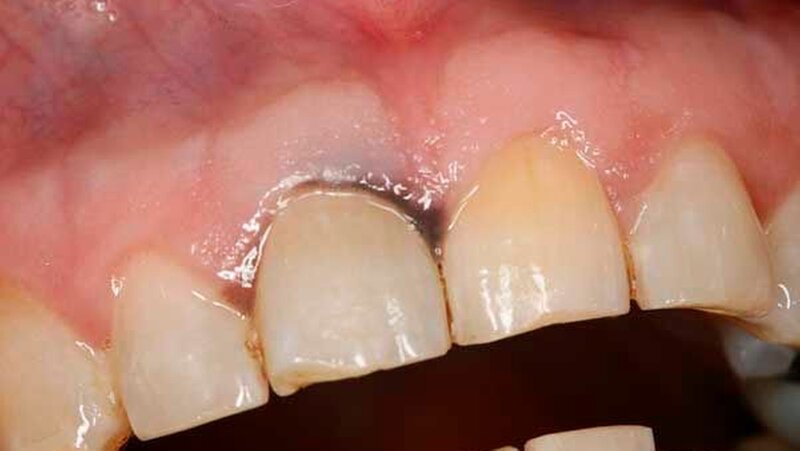

Bei der Aufnahmeuntersuchung zeigte sich eine schwärzliche, circa 2 cm x 1,5 cm messende, unregelmäßige Makula der Mundschleimhaut mit unscharfer Begrenzung, die sich von der marginalen Gingiva in regio 11 in Richtung des harten Gaumens erstreckte (Abbildung 1). Die sonografische Untersuchung der Halsweichteile war unauffällig, die Panoramaschichtaufnahme zeigte einen konservierend und prothetisch suffizient versorgten, altersentsprechenden Normalbefund. Die Schleimhautveränderung war bereits klinisch hochgradig verdächtig auf ein Mundschleimhautmelanom.